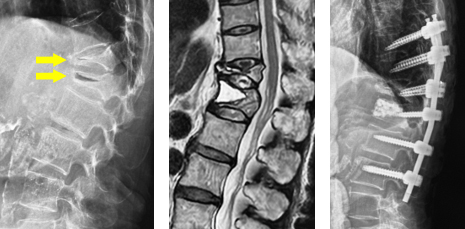

(左)第12胸椎および第1腰椎の骨粗鬆症性椎体骨折を認めます。(中)MRIでは第1腰椎に大きな骨欠損を認め、骨折が難治性で不安定であることを示しています。(右)第1腰椎に椎体形成術を施行し、さらに骨が脆かったため、頭尾側にスクリューを挿入して固定しています。